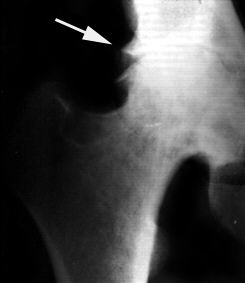

Рентгенологическая семиотика остеоартроза складывается из признаков, отражающих дистрофические изменения в суставных хрящах (сужение суставной щели) и в костной ткани (уплощение и деформация суставных поверхностей, кистевидные образования), нестабильность суставов (подвывихи, искривления оси конечностей), реактивные компенсаторно-приспособительные процессы (краевые костные разрастания, субхондральный остеосклероз).

Ранним рентгенологическим симптомом являются краевые костные разрастания — остеофиты — следствие активной пролиферации периферических отделов суставного хряща. Они проявляются вначале заострением краев суставных поверхностей, а затем, нарастая, образуют массивные костные шипы и губы. Краевые остеофиты, как правило, раньше обнаруживаются со стороны суставных впадин.

Сужение суставной щели свидетельствует о значительных изменениях суставных хрящей. Суставная щель может стать клиновидной, суживаясь с одной стороны и нередко расширяясь при этом с противоположной, что указывает на недостаточность связочного аппарата и нестабильность сустава.

При остеоартрозе утрачивается амортизационная функция суставных хрящей, предохраняющих костную ткань от механических перегрузок. Как компенсация развивается остеосклероз субхондральной губчатой кости. Особенно он выражен при коксартрозе в крыше вертлужной впадины, распространяясь иногда почти на все тело подвздошной кости. Однако рано или поздно этот механизм компенсации становится недостаточным. Механические силы, передающиеся непосредственно с одной суставной поверхности на другую, вызывают атрофию от давления их наиболее нагружаемых участков и прежде всего центральных отделов суставных головок. Вследствие этого они уплощаются и одновременно расширяются.

В России распространена рентгенологическая классификация остеоартроза по стадиям развития, разработанная Н. С. Коссинской:

Остеоартроз в I стадии характеризуется главным образом краевыми костными разрастаниями при незначительном сужении суставной щели;

Во II стадии она сужена более отчетливо, возникает субхондральный остеосклероз;

Резкое сужение суставной щели в III стадии остеоартроза сопровождается уплощением суставных поверхностей и развитием кистовидных образований;